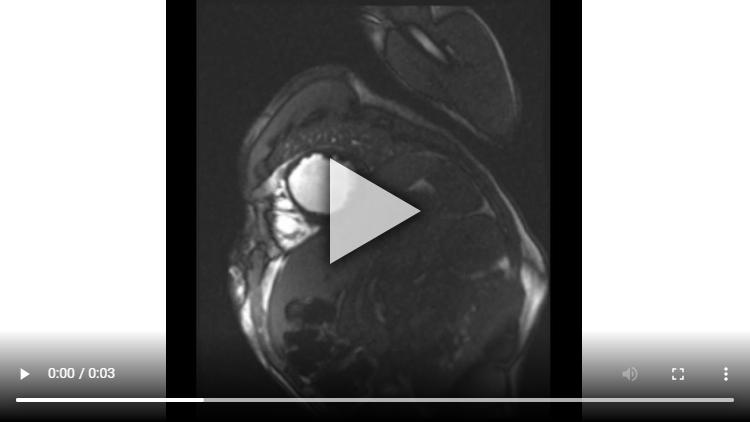

Figure 2A : Séquence de perfusion premier-passage au repos - Coupes petit-axe médian

Présence d’une hypoperfusion sous-endocardique de toute la paroi antéro-septo-apicale débordant sur la paroi apico-latérale. Cette hypoperfusion correspond à la zone de l’infarctus.

Aucun thrombus intra-VG n’est visualisé sur ces séquences de perfusion de premier passage de repos. En effet, un thrombus serait apparu sous la forme d’une masse apicale en hyposignal (noire) avec un produit de contraste qui aurait moulé le thrombus.